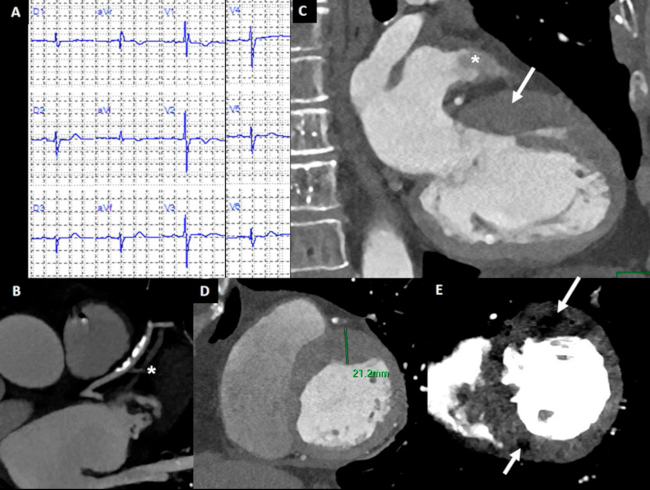

Presentó un examen físico normal y electrocardiograma sin cambios con respecto a los previos (Figura 1A). Se solicitó angioTC, que se realizó con un tomógrafo espectral (IQon Spectral CT, Philips Healthcare, Best, Holanda)® mediante una adquisición volumétrica con gatillado electrocardiográfico retrospectivo para la fase arterial (Figura 1), y con gatillado prospectivo para las imágenes de realce tardío (Figura 2) obtenidas a los 5 minutos y sin contraste adicional, utilizando técnicas de modulación de tubo para reducir la dosis de radiación. Se administró un total de 65 ml de contraste.

Las arterias coronarias principales presentaban lesiones leves calcificadas con predominio de la arteria descendente anterior, mientras que la primera rama diagonal, de muy fino calibre, se encontraba ocluida a nivel proximal (Figura 1B). Utilizando reconstrucciones en fin de diástole, se evidenció hipertrofia asimétrica del ventrículo izquierdo (VI) con predominio anterobasal y septal (Figura 1D) y discreta hipertrofia del ventrículo derecho (VD) a nivel apical (Figura 2C), e incremento de la trabeculación miocárdica del VI. La función sistólica global se encontraba conservada. Mediante la evaluación espectral, se evidenciaron áreas focales intramiocárdicas de hipoperfusión (Figura 1E).

El defecto de llenado en el nivel de la orejuela izquierda evidenciado durante la adquisición arterial (Figura 1C), resolvió completamente en la adquisición en tiempo tardío (Figura 2A), que confirmó la presencia de estasis sanguínea sin trombo en la orejuela.